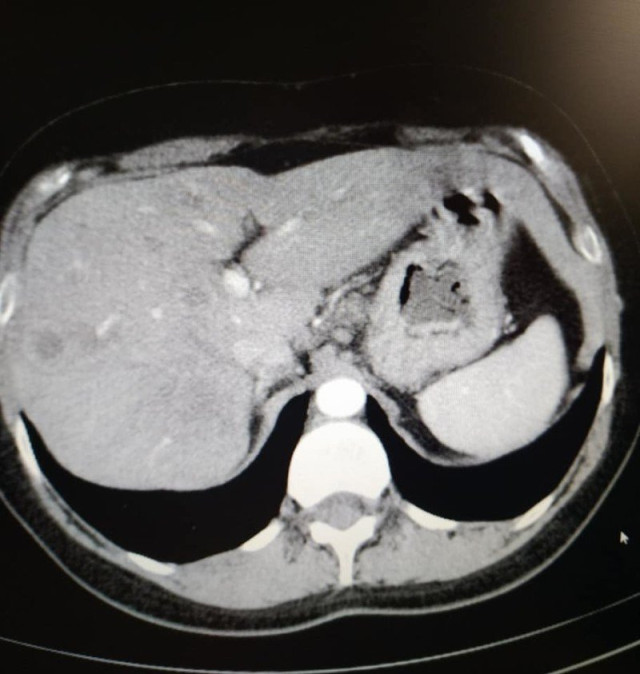

«У мене метастази, 4 стадія, але постійна від початку лікування позитивна динаміка. З 5 пухлин різних за розмірами в печінці, залишилася одна 12 на 10 мм, яка була на початку 50 мм. На першому фото печінки видно плями темні -це вони, метастази, а на другому фото теперішній стан. Це дуже успішне лікування. Ще трішки і я надіюсь і ця пухлина теж зникне», – розповіла вона.Фото печінки до лікуванняФото печінки після лікування